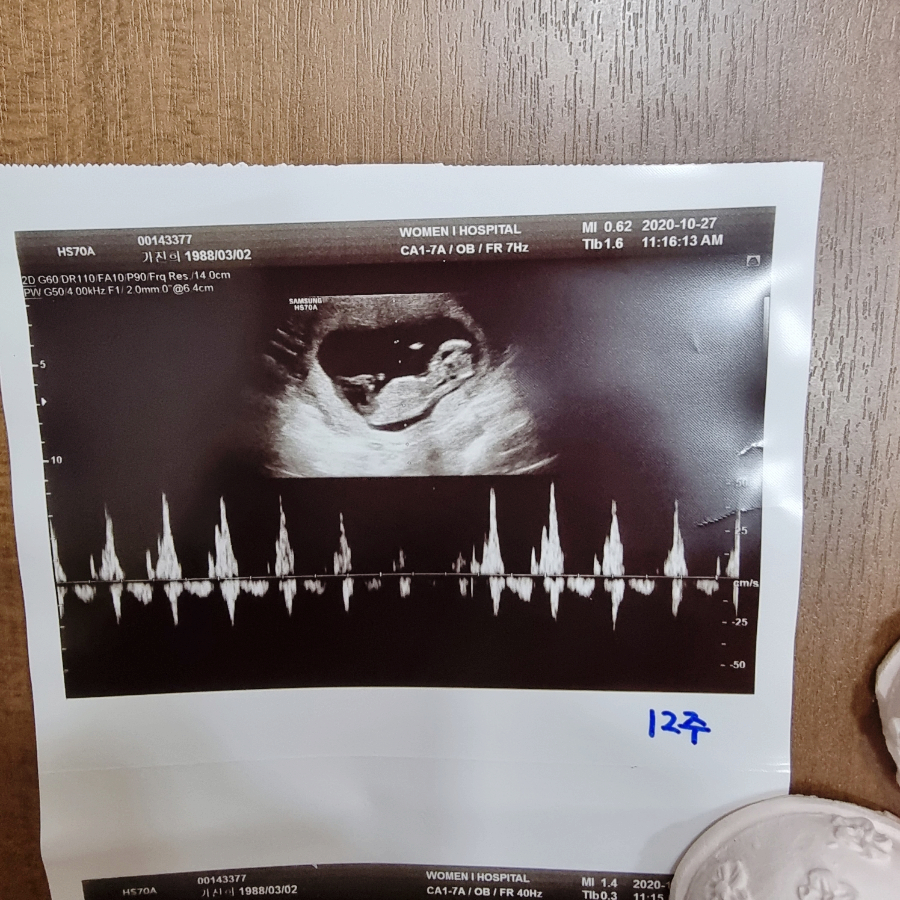

임신 4개월 12주차 초음파 사진입니다.머리의 몸체와 손발이 보이고 손톱이나 손톱도 자라는 시기입니다.심장박동음은 정상! 태아는 원래 심장이 빨리 뛰는게 정상입니다:) 제대가 정상적인 상태인지도 알 수 있습니다.

CRL: 태아의 머리에서 엉덩이까지의 길이, 태아의 크기는 6.2cm로 주수는 12주에 4일 정도, 민낯은 정말 평균 주수대로 커졌습니다.예정일은 5월 7일이라고 적혀있고 실제로 생얼은 1박 2일 유도분만 하고 5월 12일에 태어났습니다.

임신 11주 12주의 초음파 사진인데, 무엇을 찍었는지 잘 모르겠습니다.머리 같기도 하고 배 같기도 하고, 어쨌든 우리의 민낯 목둘레는 3mm 미만이고 목둘레 길이도 정상이라고 하더군요!